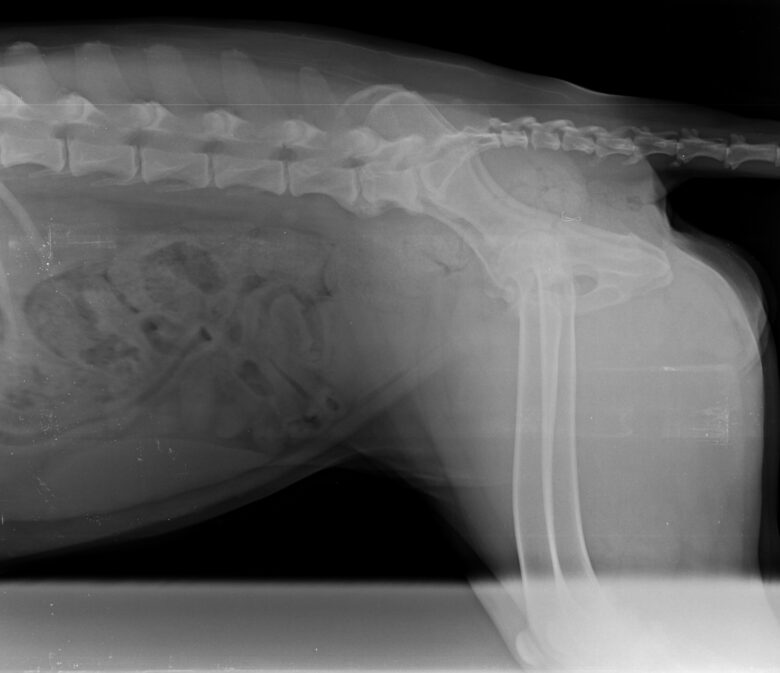

Nous avons choisi de faire une radio et c’est là que nous avons découvert l’impensable : Helly est atteinte d’une dysplasie très importante ainsi que d’arthrose et de becs de perroquet – les vertèbres se soudent entre elles et réduisent drastiquement la mobilité – à de multiples endroits.

Après un premier rendez-vous avec le spécialiste Dr Wiliam RANDLE à la Yourte Vétérinaire pour confirmer qu’Helly était éligible à cette pratique au regard de ses pathologies et des images radios, nous avons convenu d’une opération un mois plus tard début avril 2025.

L’intervention dure 30 à 40 minutes avec une sédation légère – ils n’intubent pas le chien a priori sauf exception – et le vétérinaire va venir déposer avec une grosse aiguille les implants d’or sur les zones prédéfinies. Helly a reçu 32 implants au total sur les hanches, la colonne et les poignets. A la Yourte, ils ne rasent que les zones nécessaires contrairement à d’autres cliniques qui rasent intégralement les hanches du chien par exemple.

Le mécanisme de l’arthrose est complexe : les diverses inflammations qui vont venir calcifier les os et les souder entre eux en réduisant de fait la mobilité – les fameux becs de perroquet sur la colonne – sont très douloureuses. La douleur est accentuée par le froid et l’humidité. Il est donc normal qu’un chien porteur de cette pathologie semble très raide notamment au réveil après une nuit de sommeil car il va devoir déverrouiller son corps. De la même façon, il peut l’être en rentrant d’une randonnée une fois au repos mais pas durant l’effort.